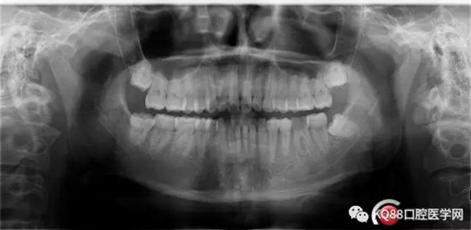

第四步:試尖片。四個根管,錐度良好,牙膠尖到位。

7.png

8.png